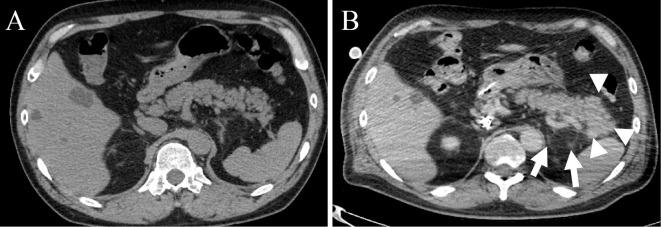

Severe coronavirus disease (COVID-19) can induce serious complications, including acute respiratory distress syndrome, septic shock, and acute kidney injury. However, few reports have associated COVID-19 with pancreatitis. We herein report the case of a 55-year-old patient who developed acute pancreatitis associated with severe COVID-19 pneumonia and was successfully treated with veno-venous extracorporeal membrane oxygenation (ECMO). Elevated pancreatic enzymes levels and computed tomography findings led to the diagnosis of acute pancreatitis due to COVID-19. Although we found that severe COVID-19 pneumonia can lead to pancreatitis, the underlying pathophysiology remains unknown.

重症冠状病毒病(COVID-19)可引发严重并发症,包括急性呼吸窘迫综合征、感染性休克和急性肾损伤。然而,很少有报告将COVID-19与胰腺炎相关联。我们在此报告一例55岁患者,该患者患与重症COVID-19肺炎相关的急性胰腺炎,并通过静脉-静脉体外膜肺氧合(ECMO)成功治疗。胰腺酶水平升高和计算机断层扫描结果导致诊断为COVID-19所致的急性胰腺炎。尽管我们发现重症COVID-19肺炎可导致胰腺炎,但其潜在病理生理学仍不清楚。